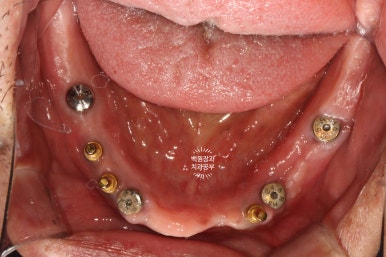

임플란트 2차수술을 하면 이렇게 임플란트 위치를 확인하실 수 있게 됩니다.

그리고 잘 유지된 각화치은의 양을 확인하실 수 있죠.

처음 내원하셨을 때 임플란트 주위염이 심했던 1개의 임플란트를 제외하고 3개의 임플란트는 이제 치아 머리를 얹어 새로운 쓰임을 기다리고 있는 중입니다.

임플란트를 몇 개 심고나니 뭔가 위치가 더 조화로워 보이지 않나요?